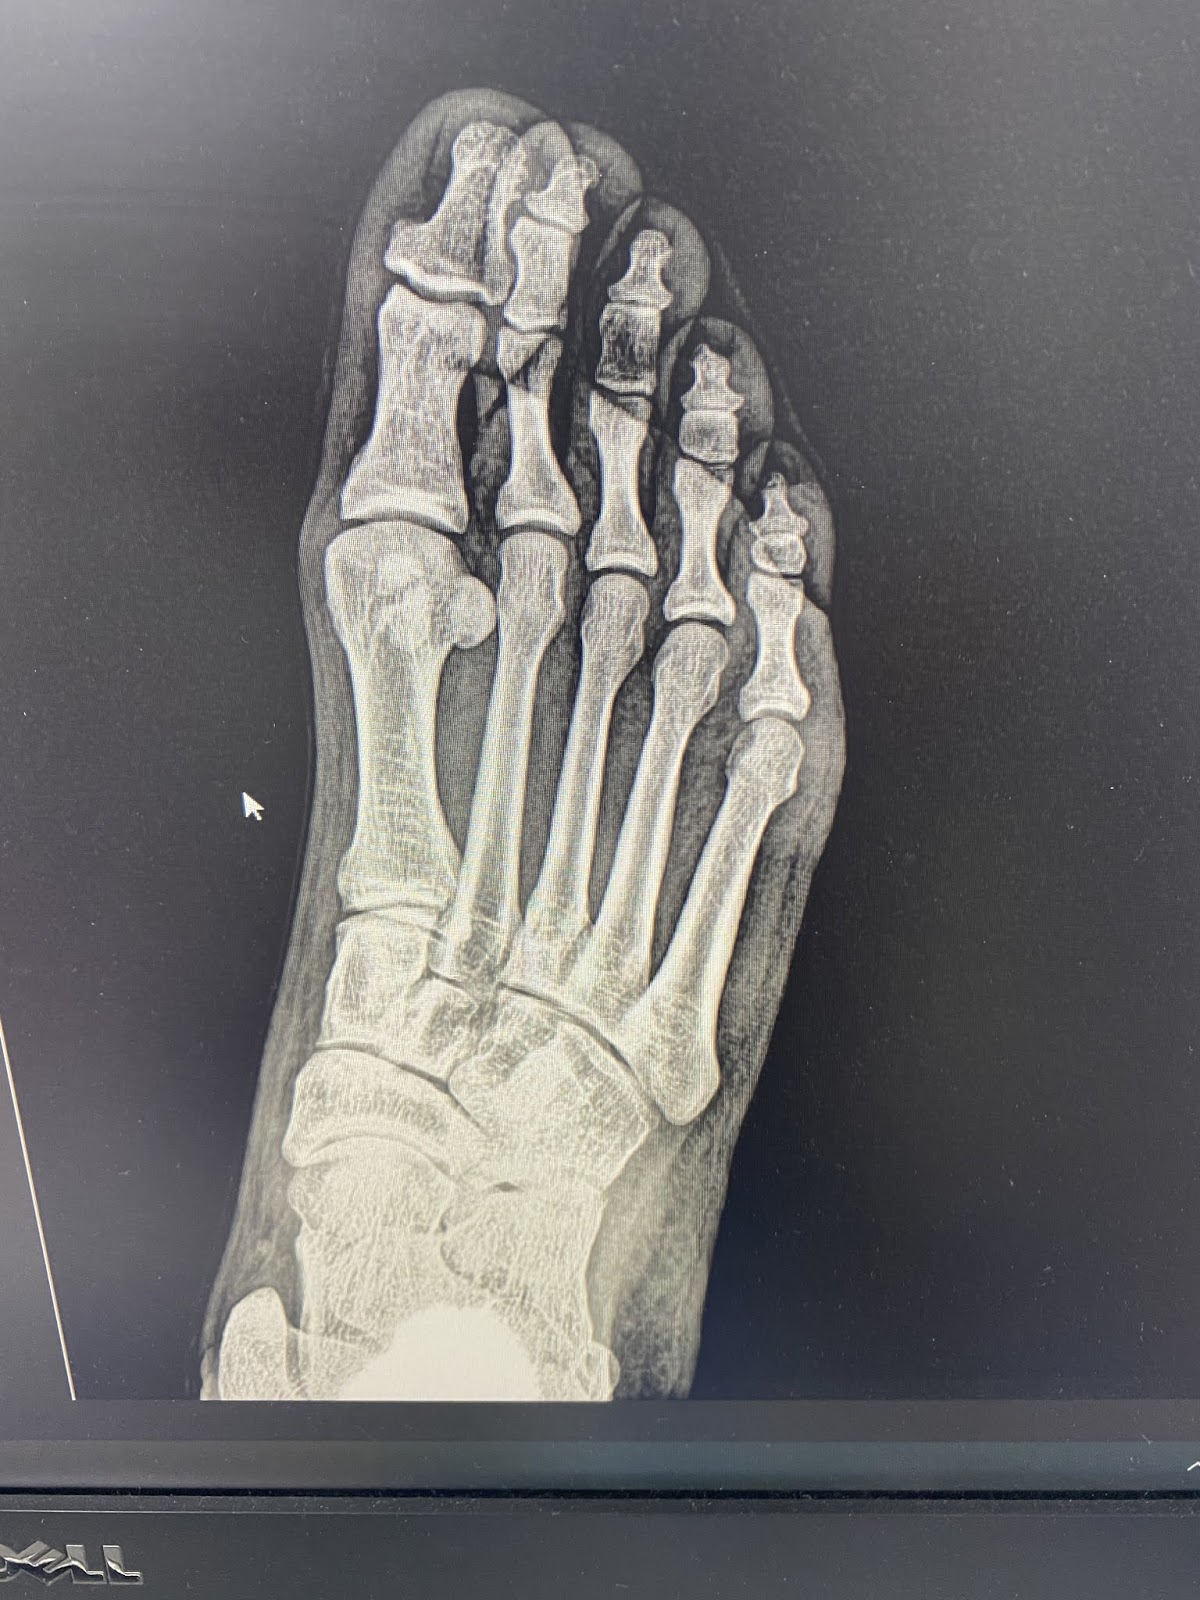

Radiology Review Sesamoid fracture Axis Sports Med Sesamoid Fracture Walking Boot With a sesamoid fracture, you will feel pain immediately after a hyperextension injury to the big toe (the toe is bent backward). Those options may include a combination of wearing shoes with more cushioning, wearing orthotic inserts that limit the motion of your big toe, taping your big toe to give added. Explore the impact of sesamoid injuries on foot. Sesamoid Fracture Walking Boot.